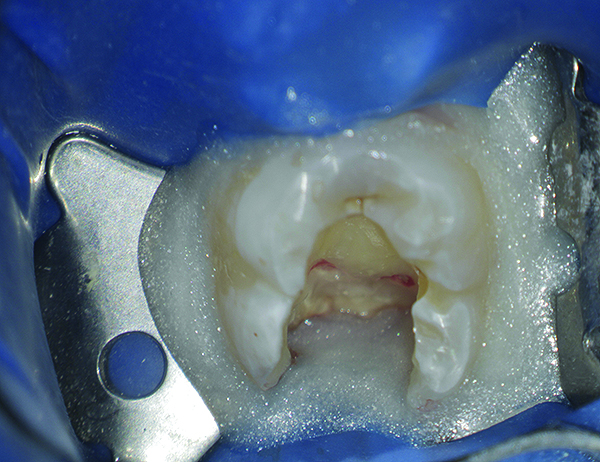

(2. and 3.) Definitive isolation with a rubber dam is enhanced and areas of crevicular fluid leakage are properly sealed with the aid of a caulking material.

Figure 3